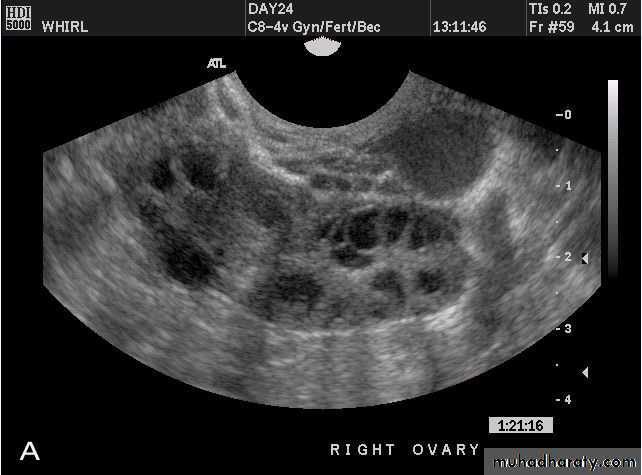

POLYCYSTIC OVARY SYNDROME

Images from women with differing expressions of the four major subtypes of the metabolic syndrome associated with polycystic ovary syndrome (A–D). The images exhibit quite differing ultrasonographic appearances in the size and distribution of follicles within PCOS ovaries. A recent corpus luteum is clearly visible in the ovary in panel (D).

• POLYCYSTIC OVARY SYNDROME

Images from women with differing expressions of the four major subtypes of the metabolic syndrome associated with polycystic ovary syndrome (A–D). The images exhibit quite differing ultrasonographic appearances in the size and distribution of follicles within PCOS ovaries. A recent corpus luteum is clearly visible in the ovary in panel (D).• POLYCYSTIC OVARY SYNDROME

Images from women with differing expressions of the four major subtypes of the metabolic syndrome associated with polycystic ovary syndrome (A–D). The images exhibit quite differing ultrasonographic appearances in the size and distribution of follicles within PCOS ovaries. A recent corpus luteum is clearly visible in the ovary in panel (D).The Oviduct (Fallopian Tube)